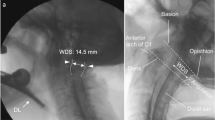

This prospective study included patients aged 20–80 years of American Society of Anesthesiologists’ physical status I–III who were undergoing elective anterior cervical spine surgery and scheduled to receive general anesthesia with NTI as requested by the surgeon. Patients at risk of pulmonary aspiration of gastric contents, with abnormal coagulation function, with pathology of the nasal cavity, and an unstable cervical spine; those scheduled for fiberoptic tracheal intubation; and those who refused to provide their informed consent were excluded. The patients were examined at the preanesthetic visit; scores were recorded for the modified Mallampati test and mandibular protrusion in the upper lip bite test (ULBT)30; and measurements were taken for the inter-incisor distance during mouth opening, for the thyromental and sternomental distance upon neck extension, for the ratio of height to thyromental distance, for the range of motion of the atlanto–occipital joint, and for neck circumference. A single investigator evaluated all patients before surgery.

Study interventions